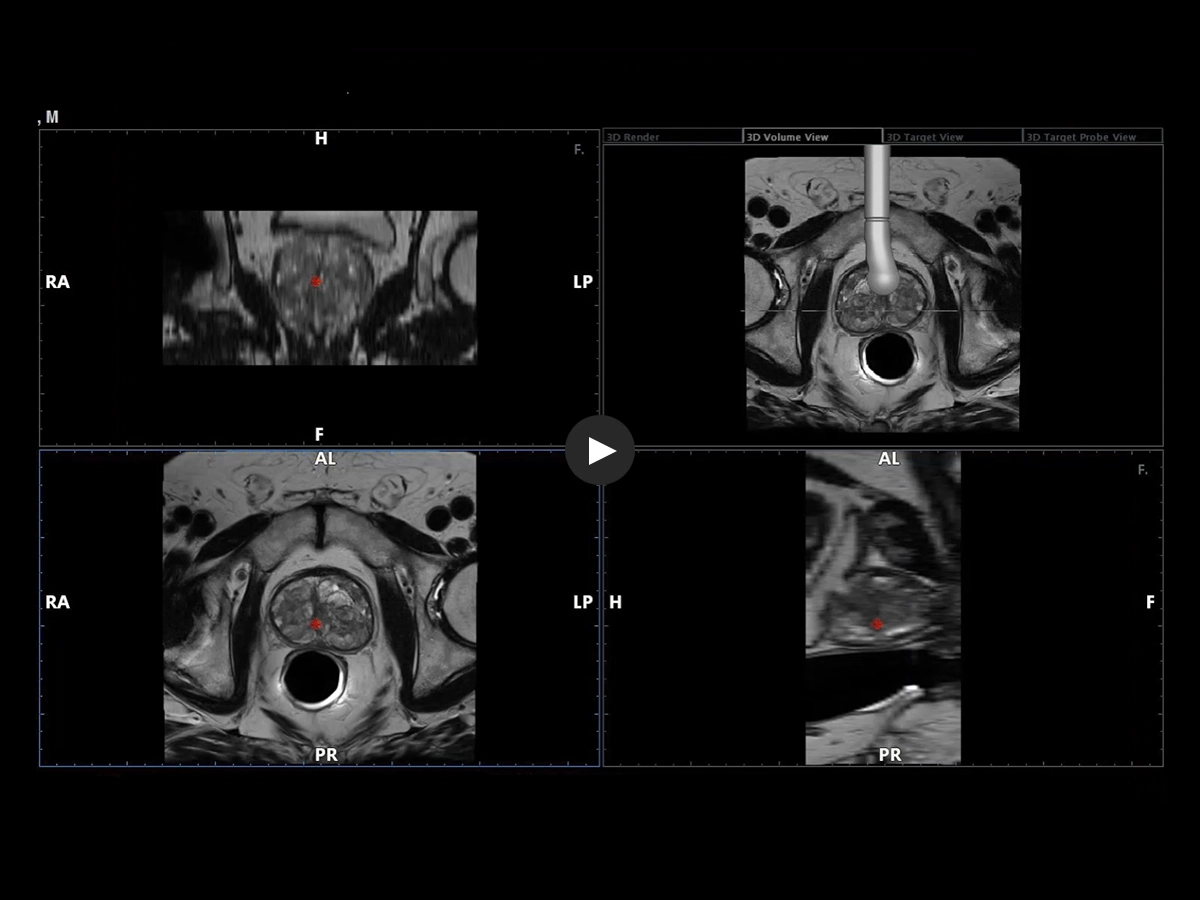

Expert users and beginners can now achieve a heightened degree of simplicity and precision by using UroFusion, Esaote’s cutting-edge fusion imaging solution that makes the most of the combination of US and MR or PET modalities.

By harnessing Augmented Insight™ (A.I.) technology, our dedicated solution enhances workflow efficiency by Automating MR Prostate Contouring & Segmentation with instant and automatic US-MR Synchronization, applied to both transperineal (TPUS) and transrectal (TRUS) prostate biopsy approaches.

Using UroFusion, clinicians will benefit from our intuitive tools to fasten the fusion procedures: the automatic prostate contouring and biopsy sample mapping are certainly the most impressive.

UroFusion seamlessly offers the ability to combine different mpMRI series, facilitating the identification of suspicious prostate lesions.

mpMRI targeting phase of PI-RADS 5 peripheral lesion

The targeted and systematic biopsy samples will be automatically saved in a 3D prostate rendering volume, a complete and clear report is automatically completed and attached to each procedure.

Transperineal & transrectal targeted biopsy (based on a 3D prostate reconstruction & sample mapping) - UroFusion report - Automatically generated